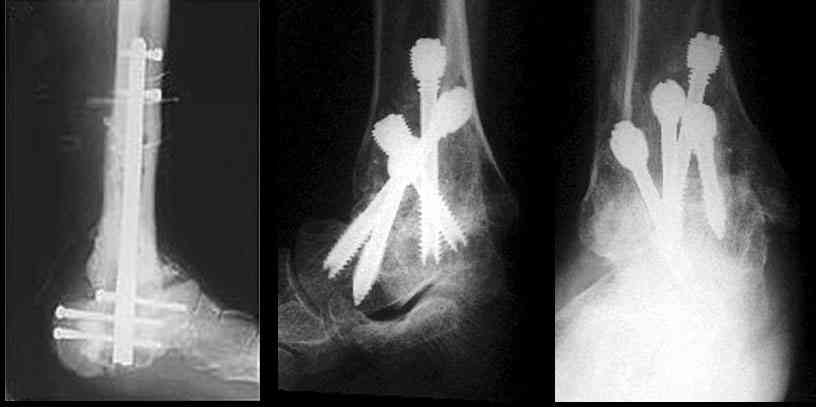

Можно: 65-летняя пациентка, оперирована по поводу несросшегося в гипсе перелома лодыжек с патологической вальгусной установкой стопы и выраженным нарушением опрной функции. Оперирована через 6 месяцев после травмы. Рентгенограммы через 4 месяца после операции.

С уважением, А.Семенистый.

Уважаемый А.Семенистый. Складывается впечатление, что вы выполнили трехсуставный артродез, уж больно длинные блокирующие винты. Не мешают ли они пациентке при ходьбе?

С увважением Ramil

Отправитель: Алексей Семенистый 05 Апрель 2007, 14:40

Да конечно винты длинноваты! Мешают ли ходить? Во всяком случае субьективно пациентка удовлетворена. Ходит, естевственно, хуже чеи до травмы, но намного лучше, чем до операции.